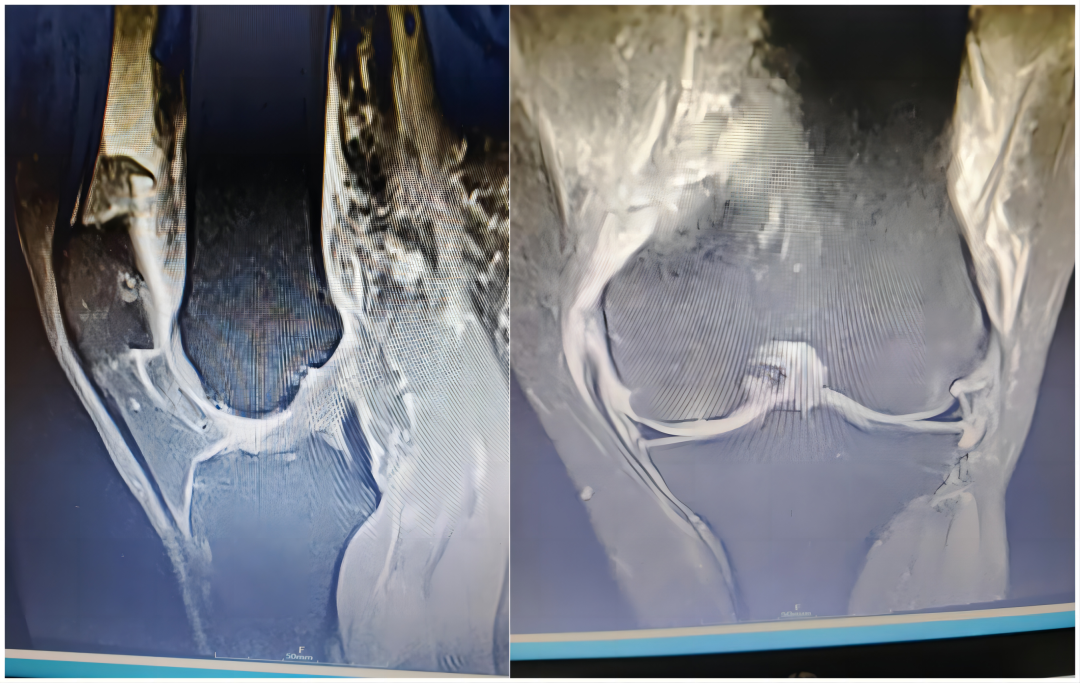

隨著醫(yī)學(xué)的不斷發(fā)展,骨科的部分手術(shù)也一改往日的“粗放”開刀,向微創(chuàng)化發(fā)展。近日,一老年女性患者劉某,因外傷致左膝腫痛入院,經(jīng)詳細(xì)查體,結(jié)合MRI檢查,考慮左膝關(guān)節(jié)內(nèi)側(cè)副韌帶斷裂、前交叉韌帶損傷、半月板損傷及股骨外側(cè)髁損傷。膝關(guān)節(jié)損傷如治療不當(dāng)易導(dǎo)致膝關(guān)節(jié)嚴(yán)重功能障礙,影響生活質(zhì)量。 術(shù)? 前 入院后,科主任魏國華帶領(lǐng)關(guān)節(jié)骨科醫(yī)師團(tuán)隊完善檢查,深入探討,科學(xué)制定手術(shù)方案,決定行內(nèi)側(cè)副韌帶重建及關(guān)節(jié)鏡下膝關(guān)節(jié)探查清理術(shù),術(shù)后患者膝關(guān)節(jié)功能恢復(fù)良好。 術(shù)? 中 術(shù) 后 關(guān)節(jié)鏡手術(shù)是將具有照明裝置的透鏡金屬管通過很小的切口插入關(guān)節(jié)腔內(nèi),將關(guān)節(jié)腔的內(nèi)部結(jié)構(gòu)放大,觀察關(guān)節(jié)腔內(nèi)的病變情況及部位,在監(jiān)視器下進(jìn)行全面檢查和清理病損部位,開展鏡下手術(shù)操作。作為一種微創(chuàng)手術(shù)同時具有診斷和治療兩種功能,相比傳統(tǒng)手術(shù)具有創(chuàng)傷小、出血少,恢復(fù)快、診斷準(zhǔn)、操作精、處理全、外觀美等優(yōu)點(diǎn),是骨科理想的診斷與微創(chuàng)手術(shù)治療方式。 主要用于治療膝、肩關(guān)節(jié)的常見疾?。喝绻切躁P(guān)節(jié)炎、滑膜炎、關(guān)節(jié)內(nèi)游離體、半月板損傷、交叉韌帶損傷、肩周關(guān)節(jié)炎、凍結(jié)肩、肩峰撞擊癥、肩袖損傷等。 就診科室:酒泉市中醫(yī)醫(yī)院關(guān)節(jié)骨科 就診地點(diǎn):門診樓:205室,電話0937-2669113 住院部:綜合樓6樓,電話0937-2620311